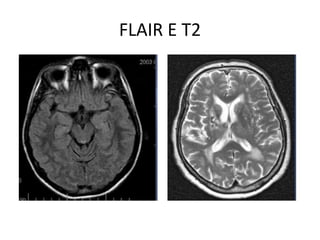

FLAIR E T2